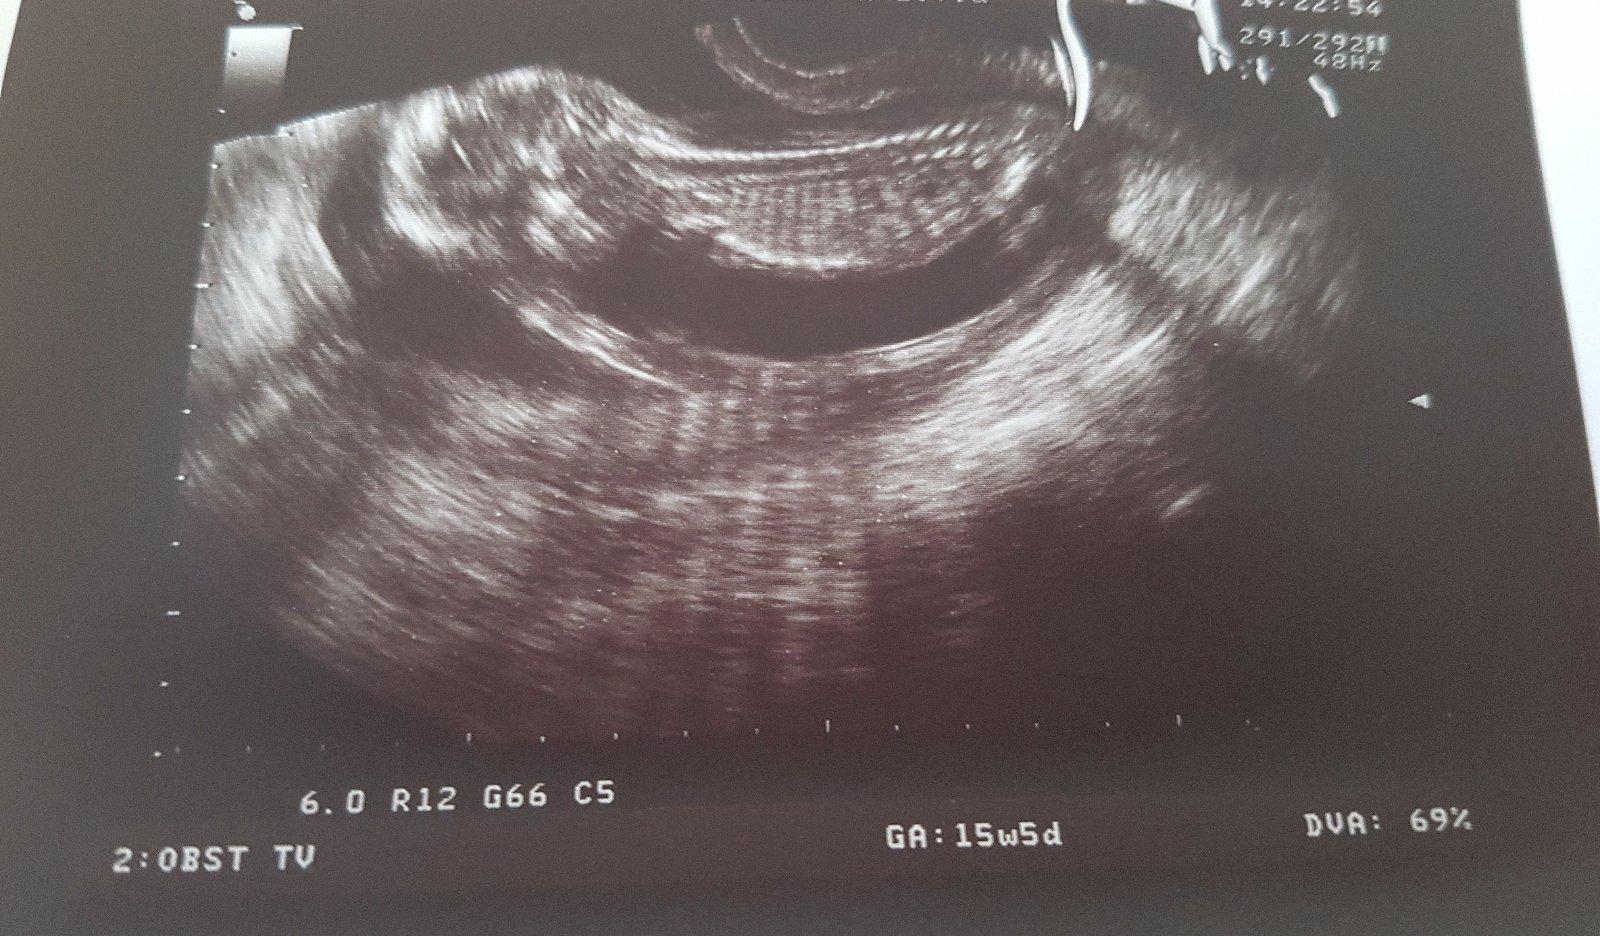

Luta13 takze sa hlasim dnes 15tt a 6dni a vcera poradna vsetko bolo v poriadku .. bude to chlapcek 😊 videli sme pipika 😊 maly sa velmi hybal tak ho dr nevedel pekne zachytit takze mame takuto fotecku 😍 o 2-3tyzdne sa chystame na 3D 😍 dakujem este raz za podporu a pomoc